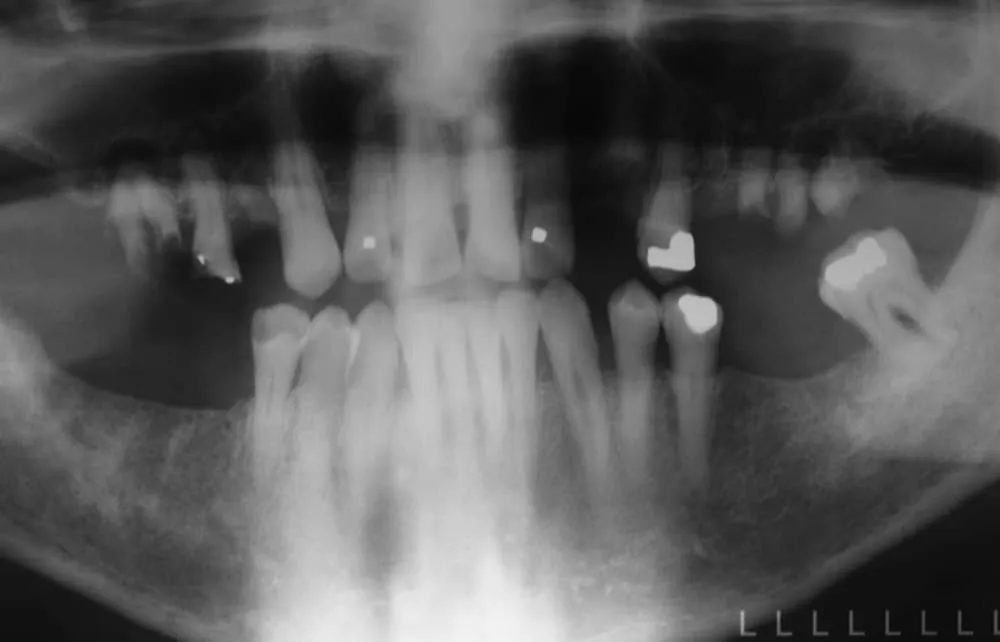

Fixed; Full Arch Restoration; Acrylic-fused-to-Metal; Fixed Partial Denture; Implant Supported and Implant Retained

Before: Failed upper remaining teeth requiring removal. Patient elected to proceed with Phase I immediate complete denture therapy with the view toward phase II implant therapy.

After: Maxillary (upper), acrylic fused to metal, fixed (hybrid) screw-retained (retrievable) restoration supported by 6 titanium root form dental implants. The restoration is fixed, therefore only Dr. Leopardi can remove it for routine maintenance and hygiene, as needed. The patient cleans the fixed restoration as he does his natural lower teeth, with a tooth-brush, floss and water-pick. The outcome is improved function, mastication/diet, aesthetics and quality of life.